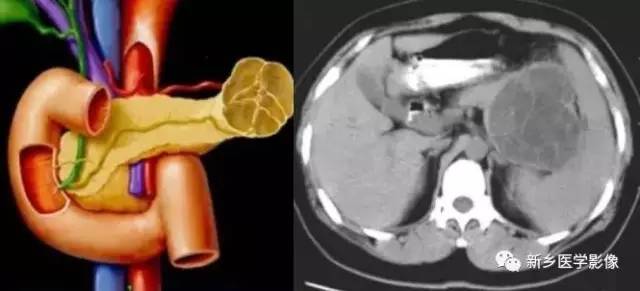

(二)黏液性囊腺瘤、黏液性囊腺癌

也多见于女性, 男女比例1 ∶2 , 40 ~ 60 岁多见。常见的症状为上腹部疼痛, 腹部肿块等,不具特征性。黏液性囊腺癌为恶性肿瘤, 而黏液性囊腺瘤有潜在恶性, 有人认为囊腺瘤和囊腺癌为疾病发展的两个阶段